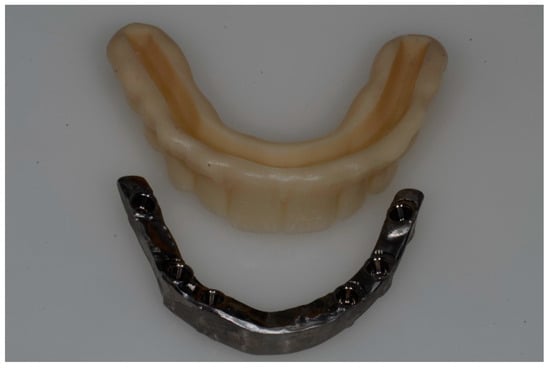

2.5. Prosthetic Protocol